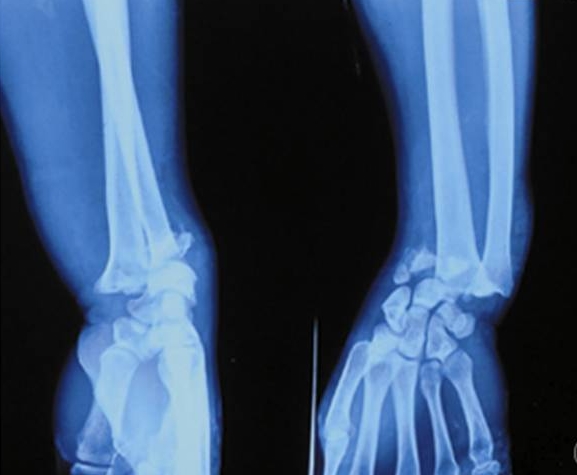

Vaikka eri karhulajit käyttäytyvät eri tavalla, voidaan niiden aiheuttamia vammoja pitää suhteellisen samanlaisina. Karhujen aiheuttamia vammoja on kuitenkin vaikea havaita arkeologisesta luuaineistosta, sillä vammat ovat voineet pääasiassa sijaita pehmytkudoksissa, jolloin kuoleman on aiheuttanut verenvuoto tai jälkeenpäin tulehdukset tai jäykkäkouristus (vrt. Floyd 1999). Toisaalta Intiassa Kashmirissa kauluskarhun aiheuttamina vammoina on raportoitu myös kallon, leukaluun, solisluiden, käsivarsien luiden sekä sormien murtumia, jotka ovat syntyneet karhun kynsien voimasta (Bhat et al. 2018; Dhar et al. 2008).